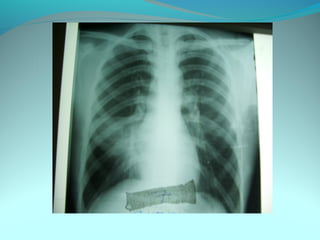

Opacité triangulaire a base cardiaque a sommet

axillaire dense et homogène

Par ailleurs on note

Une opacité plus dense que celle arrondie de 3cm de

diam hilaire gauche ;une surélévation de la coupole

diaphragmatique gauche é poche a aire gastrique

DIAGNOSTIC :

ADP hilaire gauche avec trouble de ventilation

Surelevation de la coupole G et de la poche gastrique

avec de clarté le médiastin

DIAGNOSTIC:

Hernie diaphragmatique paralysie du diaphragme